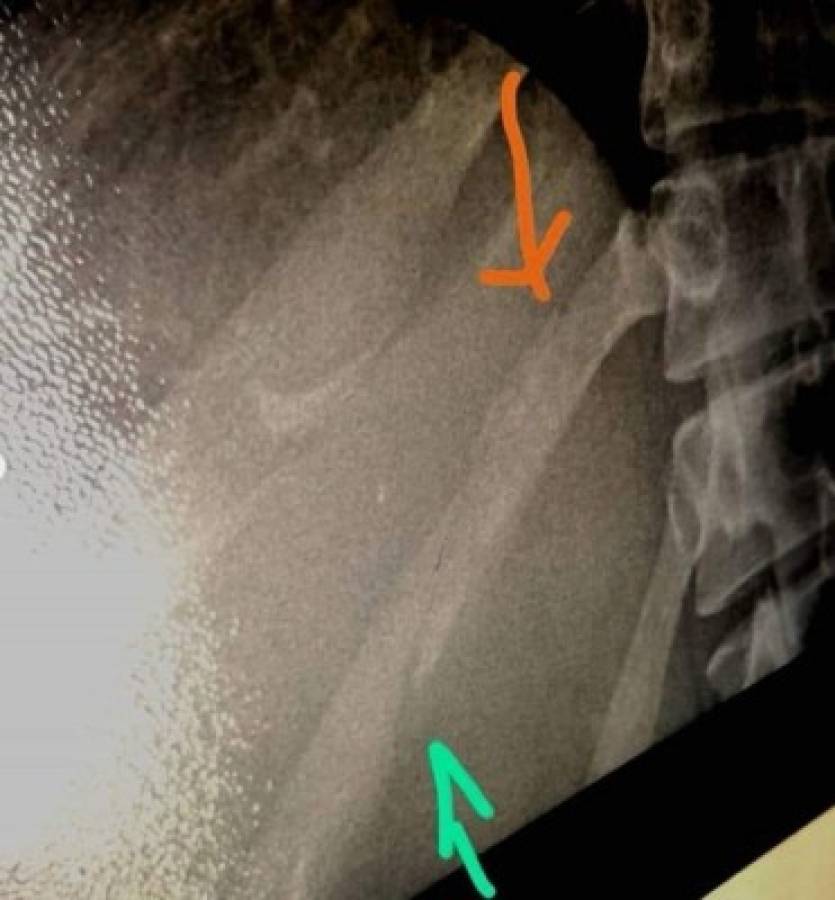

Además, acompañó un extenso texto con 10 fotografías de moretones, raspones y hasta una radiografía donde se observa una fractura en una costilla.